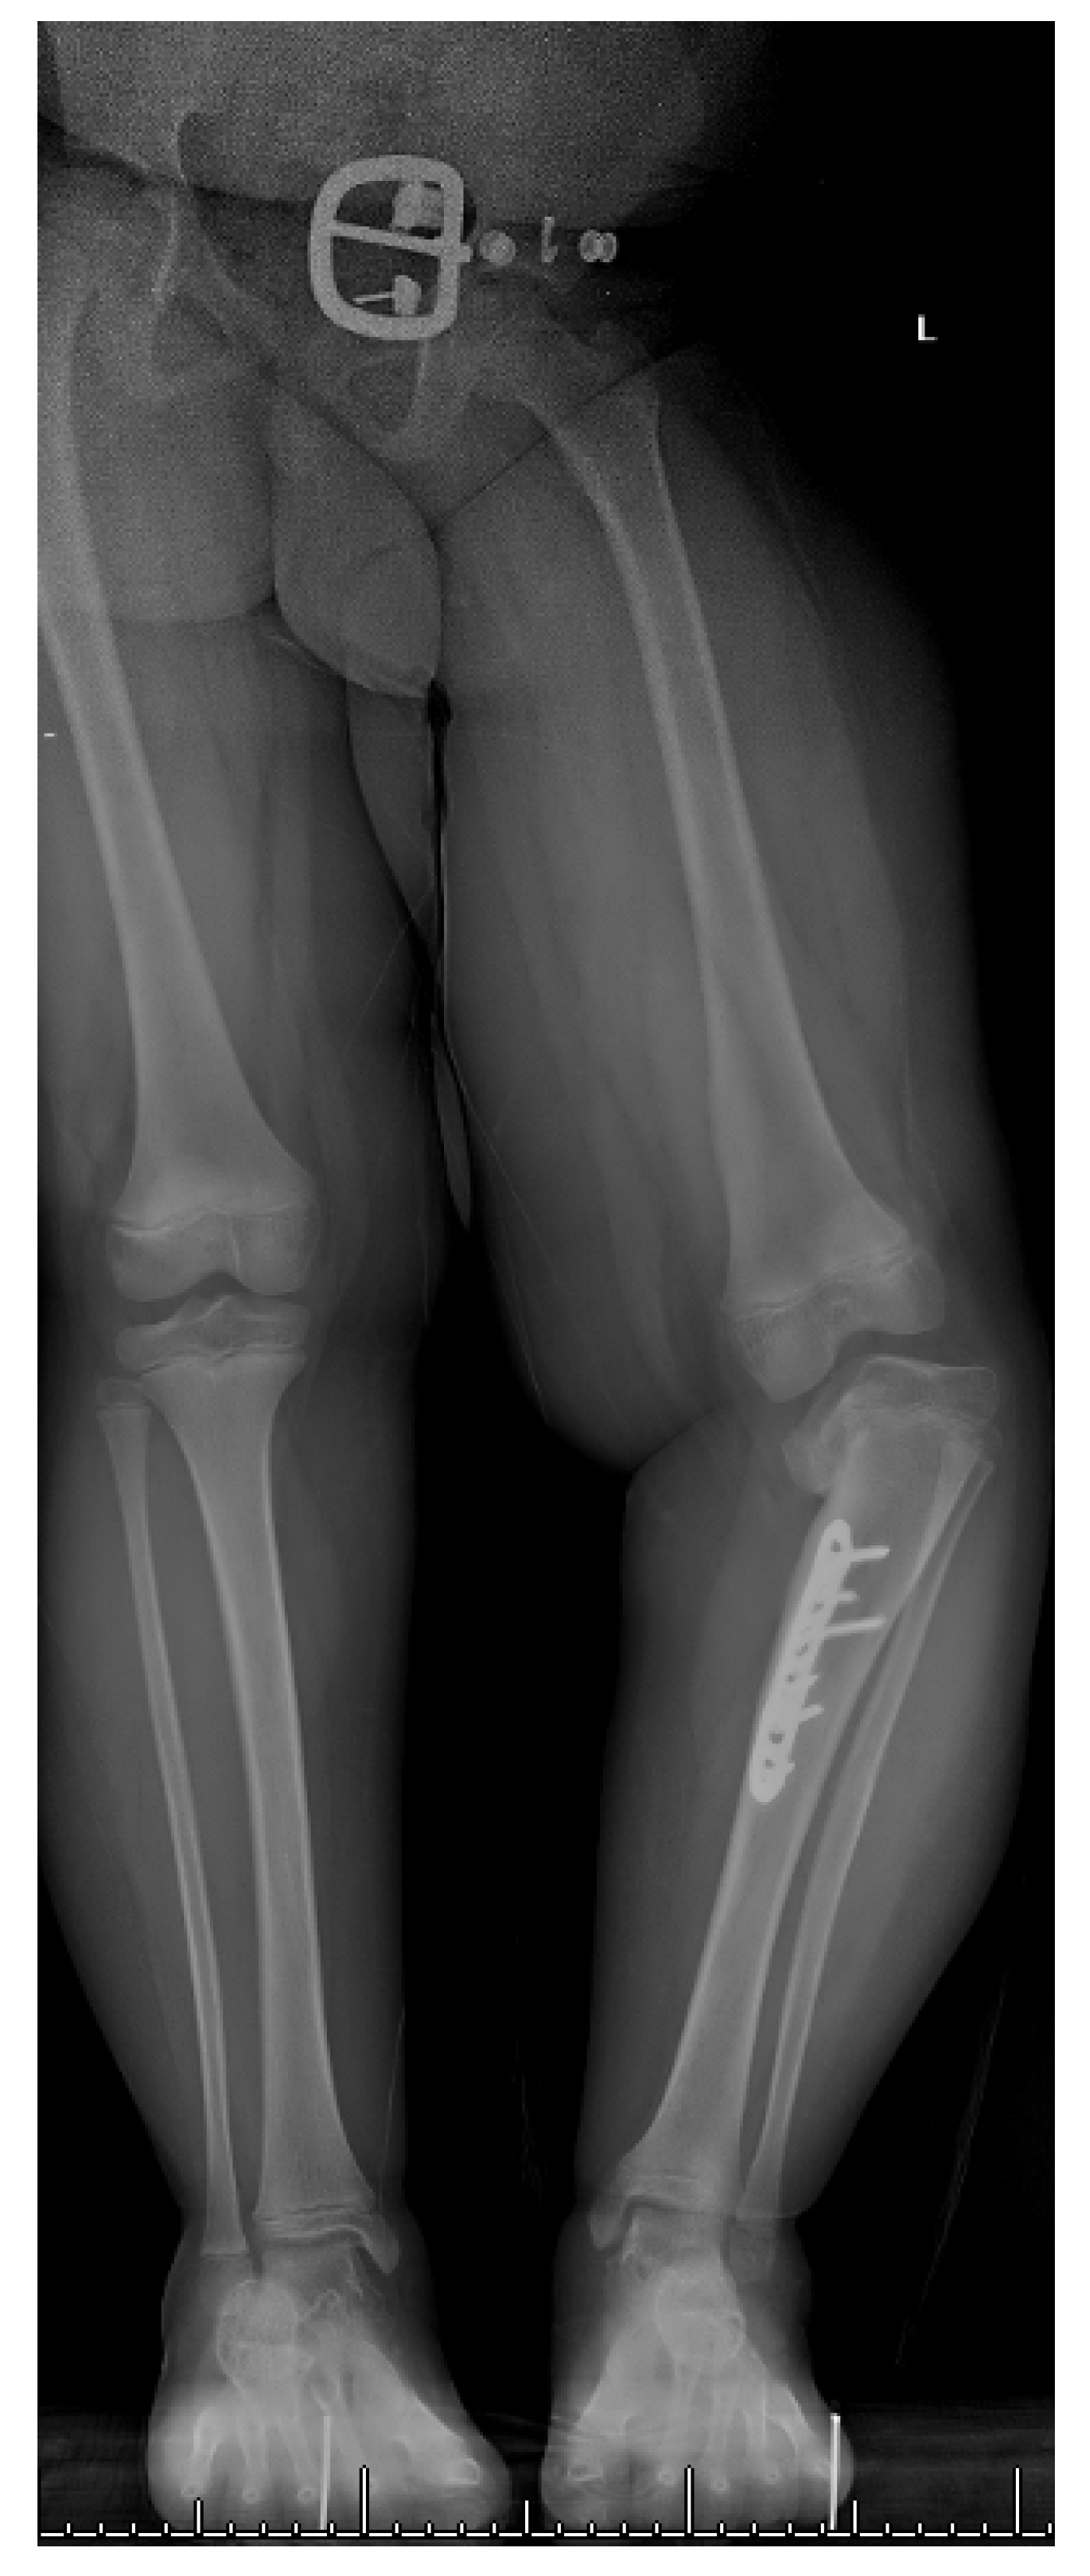

17. Gradual Correction with External Fixation